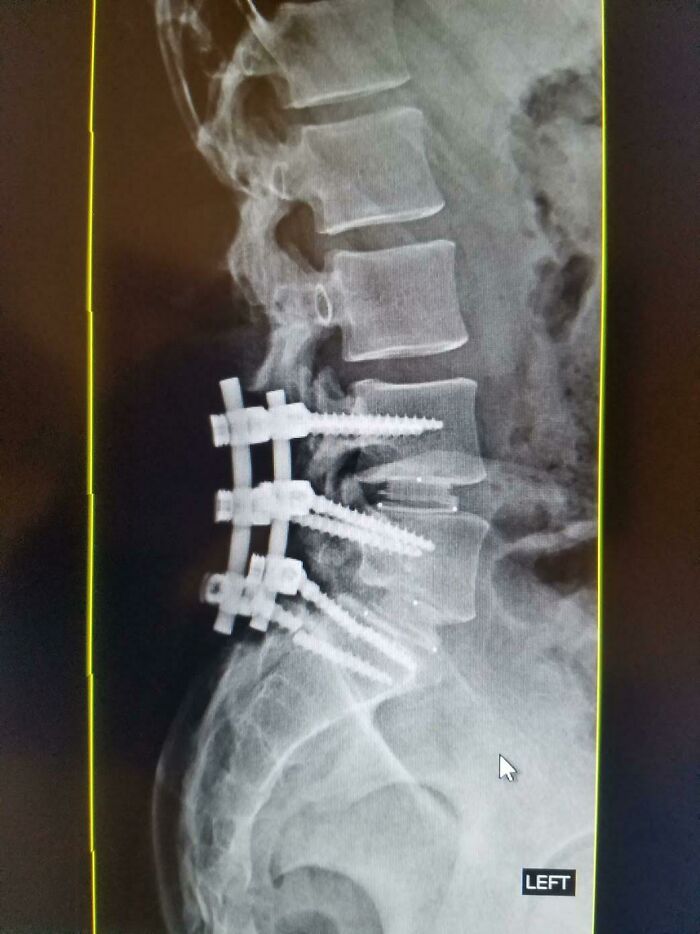

That Time I Broke One Of The Screws In My Back